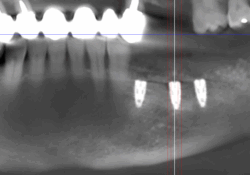

Reconstructions osseuses à visée implantaire

Lorsque l’os de la mâchoire est insuffisant pour soutenir un implant dentaire, des techniques de reconstruction osseuse peuvent être nécessaires. Ces procédures permettent d’augmenter le volume osseux pour garantir la stabilité de l’implant.

- Greffe osseuse : Ajout d’os ou de matériaux pour augmenter le volume osseux.

- Régénération Osseuse Guidée : Stimule la repousse osseuse grâce à des biomatériaux.

- Sinus Lift : Augmentation de l’os dans la région des molaires supérieures par élévation des sinus.